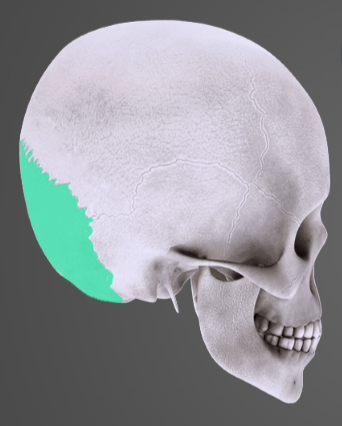

O kterou kost se jedná?

kost lícní

kost spánková

kost temenní

kost čelní